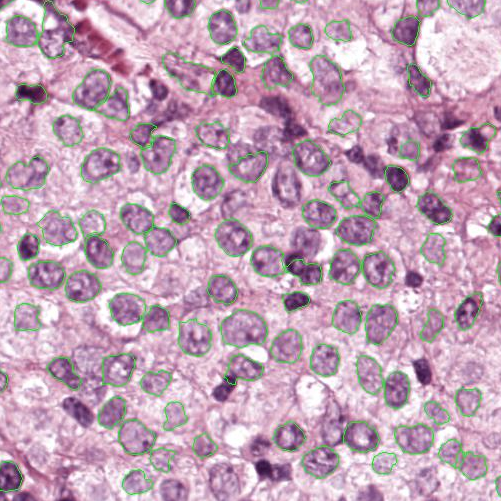

As an essential part of digital pathology, histopathology image analysis is playing increasingly important role in cancer diagnosis, which can provide direct and reliable evidence to diagnose the grade and type of cancer. This paper deals with nuclei segmentation, an important step in histopathological image analysis. The purpose of nuclei semgentation is not only counting the number of nuclei but also obtaining the detailed information of each nucleus. So unlike nuclei detection, here the outputs are the contour of each nucleus instead of only the position of their central points. Hence we can exactly extract each nucleus from the image and make it available for further analysis. For example, the features of the individual nucleus and the distribution of nuclei clusters can be used to grade and classify status of breast cancers [3, 4]. Because of appearance variation such as color, shape, and texture, nuclei segmentation from histopathological images could be very challenging, as illustrated in Fig.1, in which it is very challenging even for human to recognize and segment all nuclei within the images. Fig.1(a) and Fig.1(b) illustrate two histopathological images from different organs. Fig.1(c) and Fig.1(d) are two histopathological images from same organ but have different cancer grade.

Figure 6 shows how our method segments the nuclei step by step. The color variety is well controlled by the color normalization procedure. The prediction result shows clear nuclear areas and nucleus boundaries. In the final segmentation result and ground truth image, each nucleus is represented by a different color.